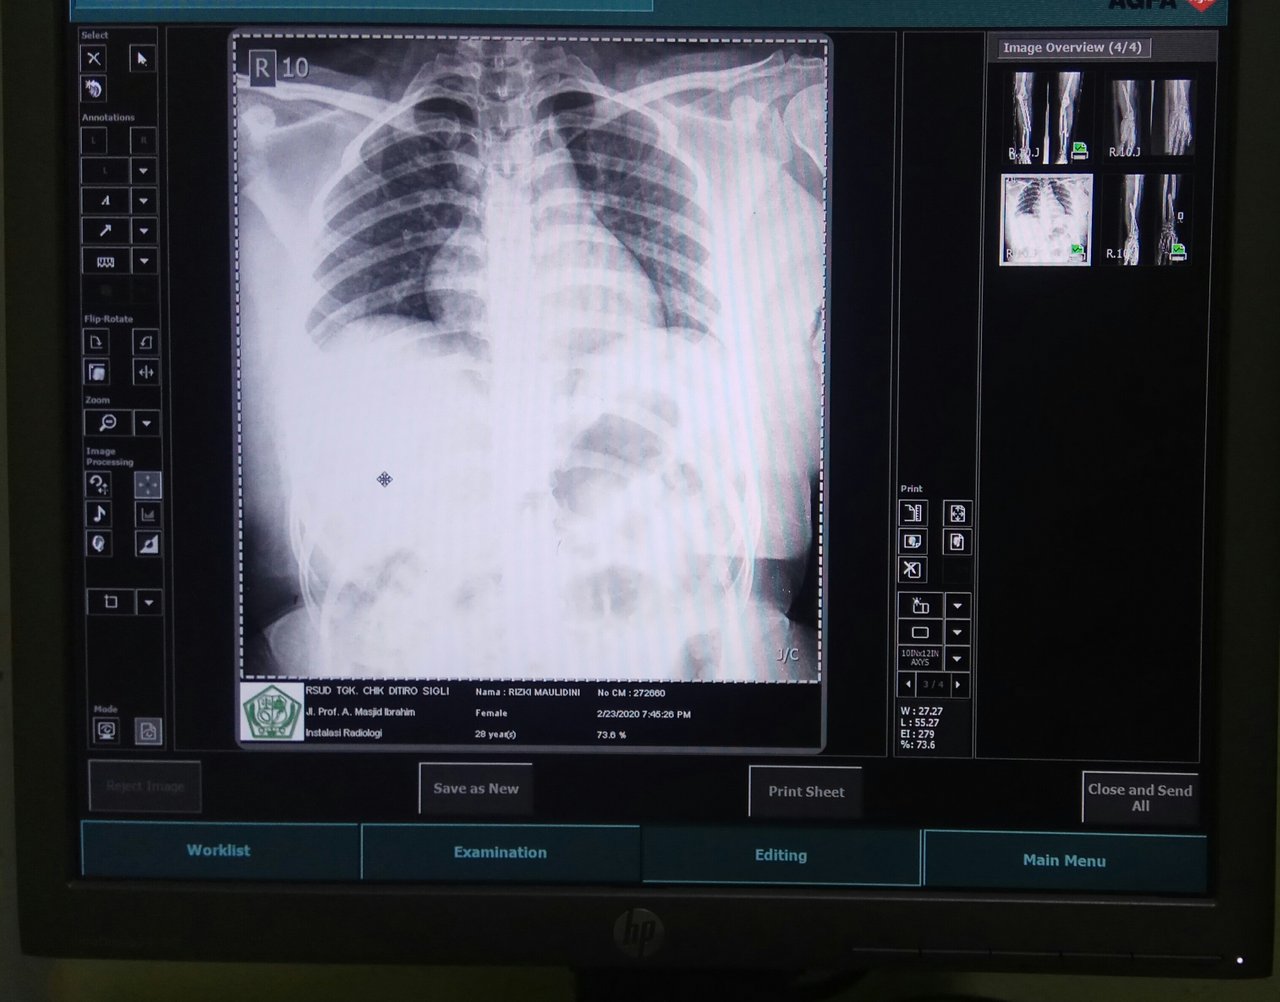

The woman was diagnosed with fractures in the right arm and left arm. Also experiencing dislocation on both wrists. It also experienced pain in the chest. So the doctor in charge of the emergency department requested a radiological examination of these organs.

The first is that I examine my left arm and left wrist. Then I did a check on his right arm and right wrist. After that I asked the patient's family to take off the patient's clothes and use the replacement clothes that we had provided. Because I have to do an inspection on the chest. In addition to clothes, also must be removed BH. Also the necklace must be removed. This is so that later in the image produced after radiological examination, there is no shadow of these objects.

After completing radiological examination, the resulting image showed that this woman had fractures in both arms and also had dislocations on both wrists. While in the chest and ribs there is no visible abnormality.